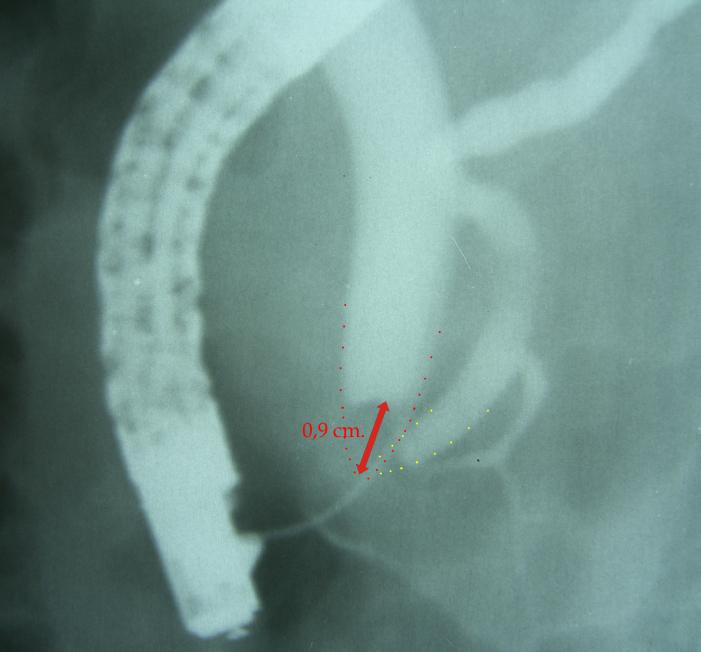

12 patients were selected (F:M, 5:7, age range 37 - 68 years) with ampullary adenoma, treated by endoscopic papillectomy. Biliary sphincterotomy was performed in 6 cases; and pancreatic sphincterotomy was performed in 3 cases. Biliary stenting was performed in 2 cases; pancreatic stent was placed in 11 cases.

En bloc resection was performed in 8 cases, and piecemeal resection in 4 cases. Complete resection R0 was noted in 10 cases. Pathology examination has show: tubulo-villous adenoma (5 patients); villous adenoma (4 patients), tubular adenoma (2 cases), adenocarcinoma (one case). Complications were immediate: bleeding (2 cases) and pancreatitis (1 case). Follow-up endoscopy reveals no ductal stenosis or recurrence.